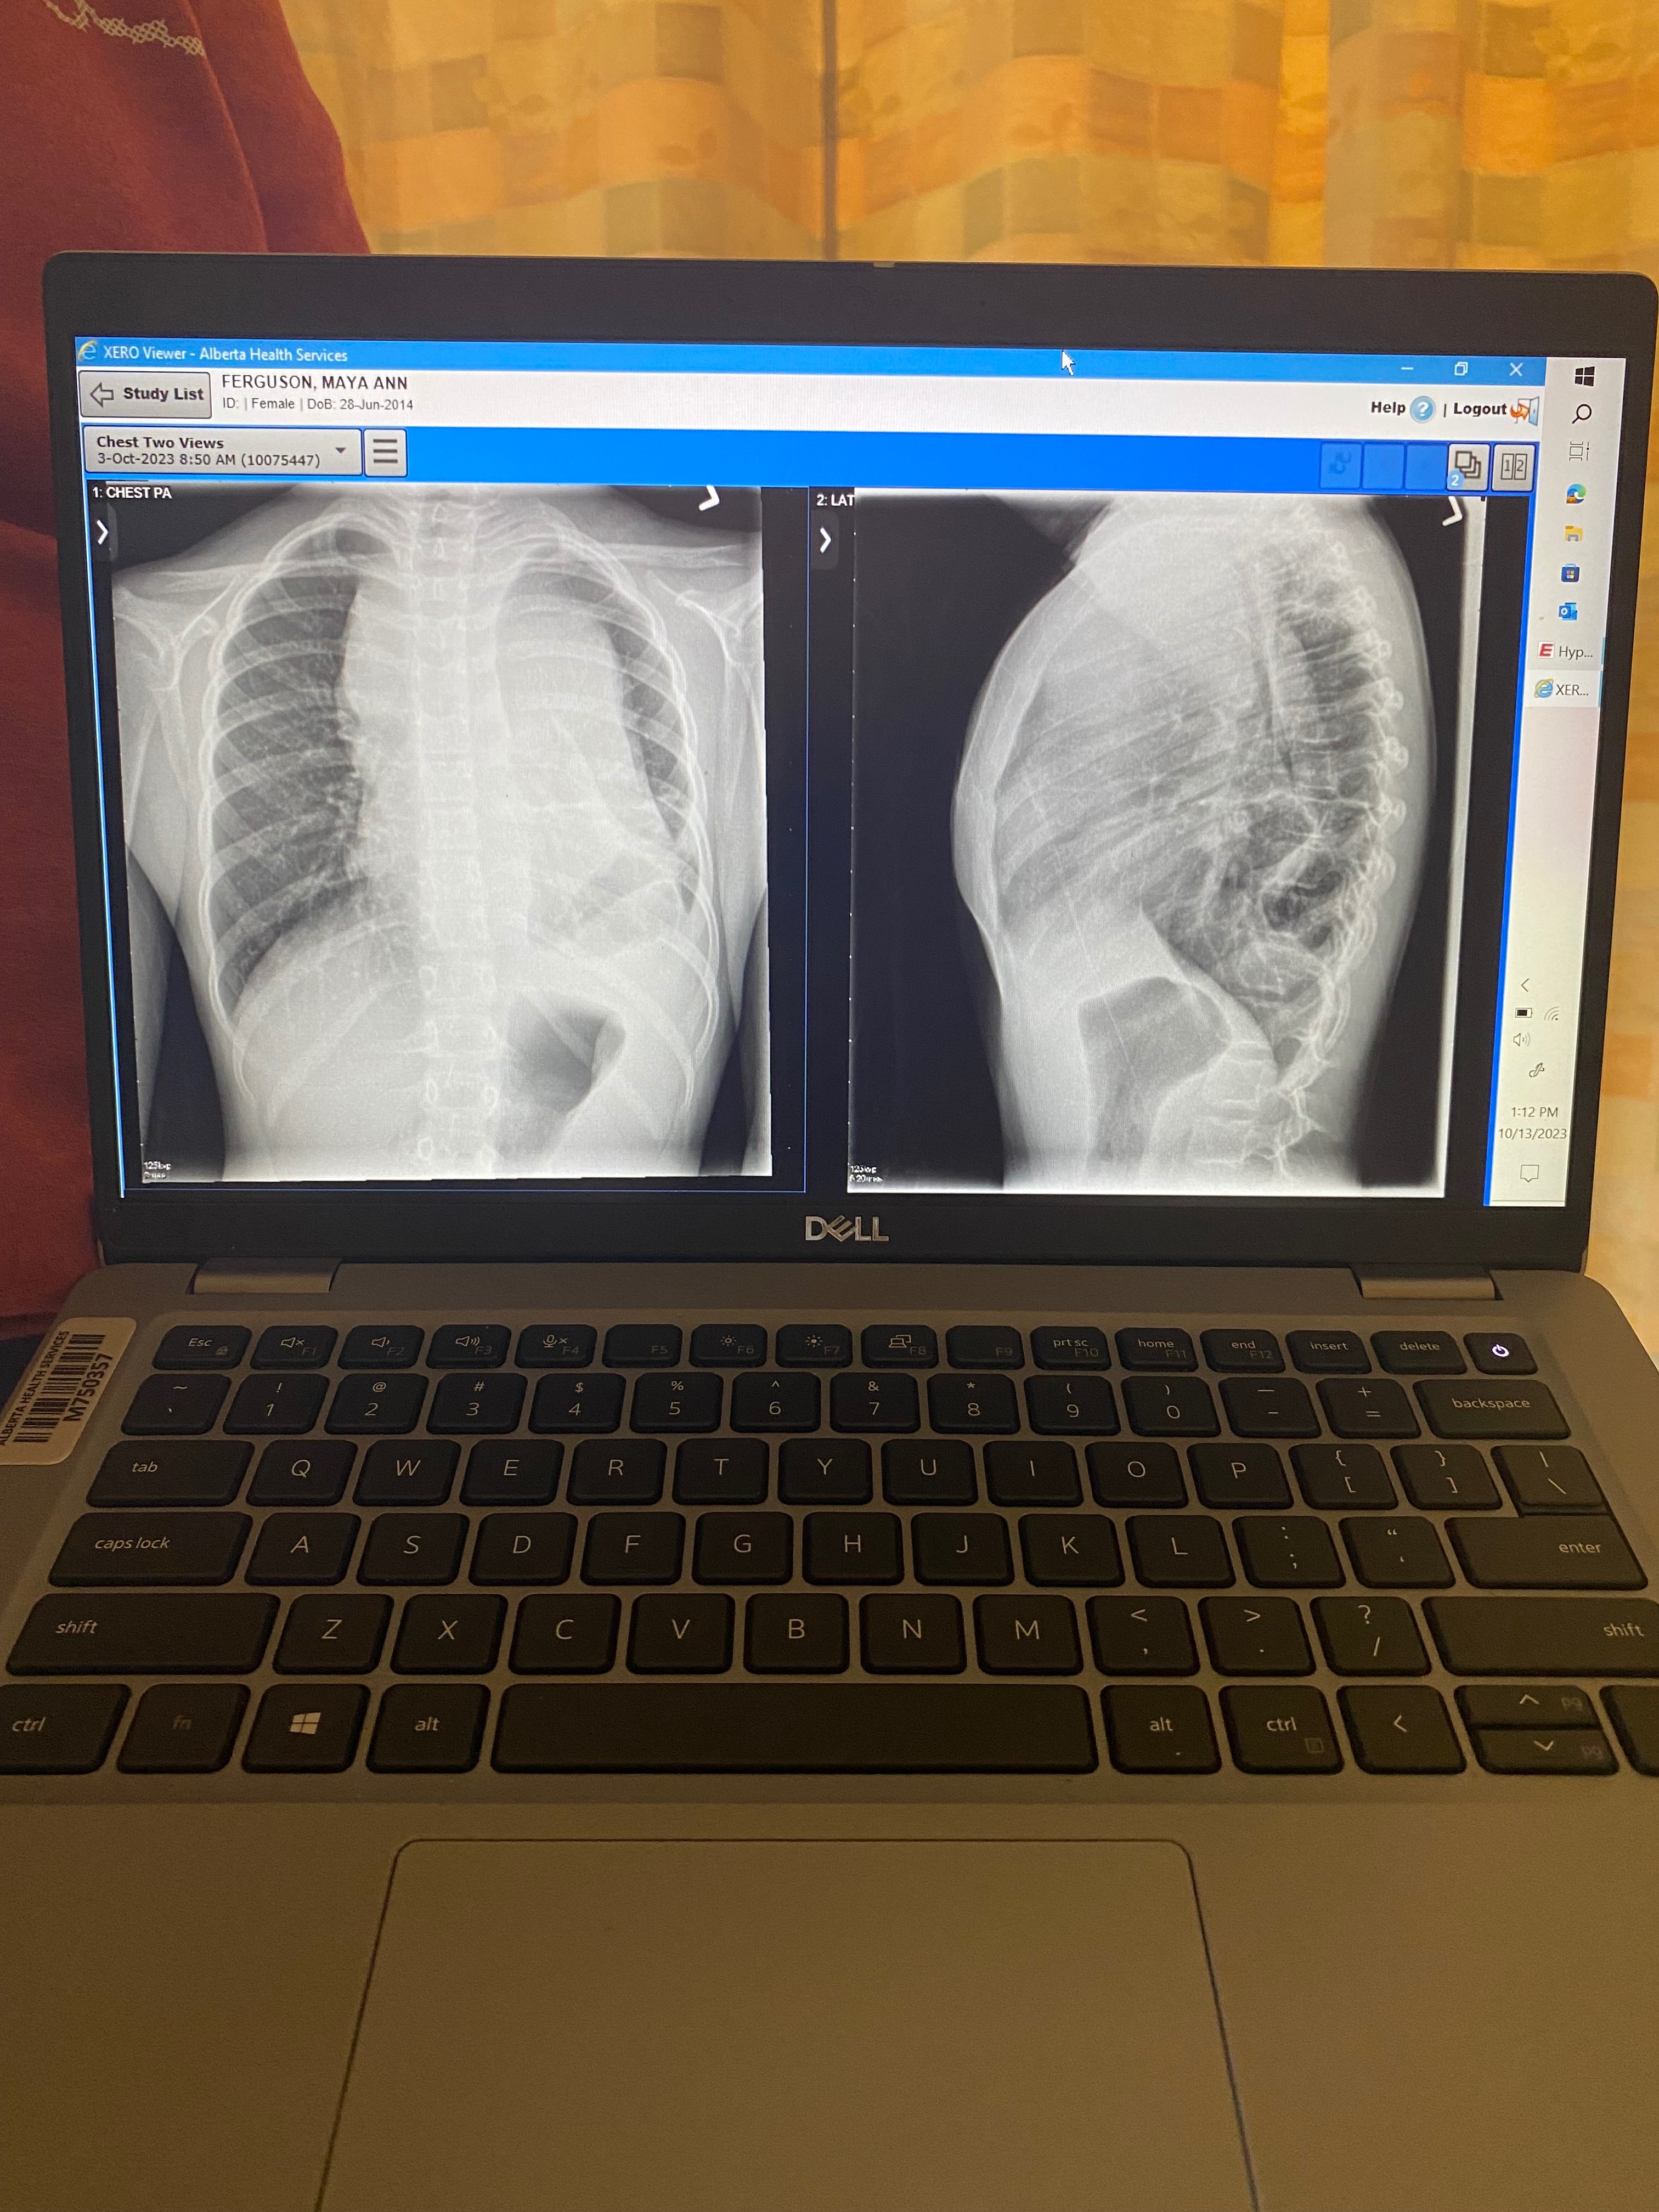

On October 4, 2023, our brave Maya — only 9 years old at the time — was diagnosed with Stage 4 T-Cell Lymphoma. Doctors discovered a large mass covering the left side of her chest and spreading to the right. It was every parent’s worst nightmare.